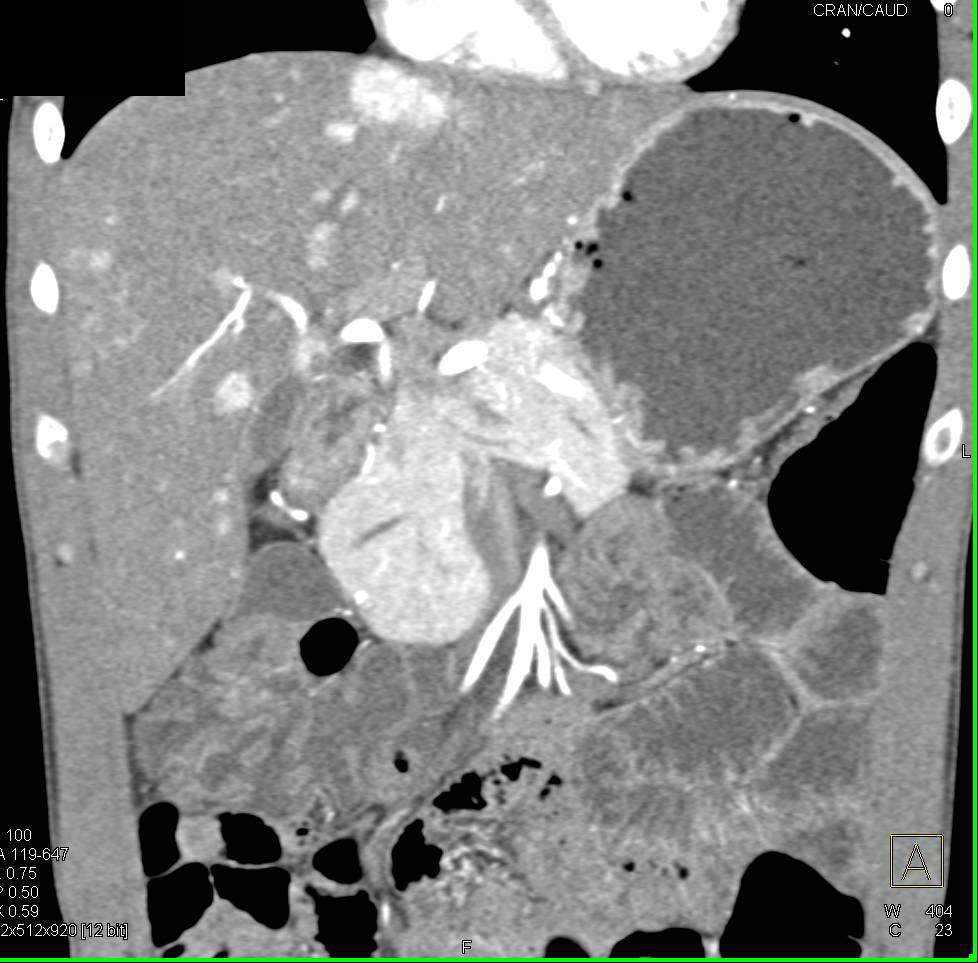

Neuroendocrine Tumor of the Pancreas Involves the Head of the Pancreas